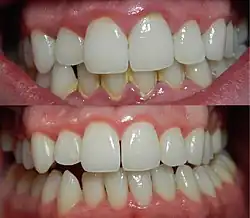

Gingivite sévère avant (haut) et après (bas) un débridement mécanique des dents et des tissus gingivaux adjacents